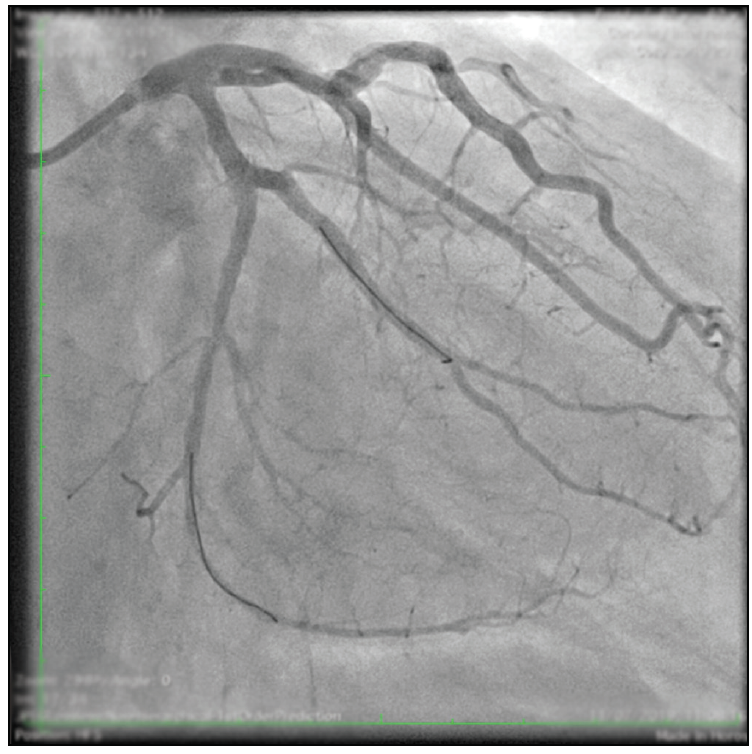

A 62-year-old man with non–insulin-dependent diabetes and no cardiac history was diagnosed with angina pectoris Canadian Cardiovascular Society grade II by means of a positive stress echocardiogram at the inferior and posterior left ventricular wall with normal systolic function. Diagnostic angiography revealed two-vessel disease: a severely calcified subocclusive lesion in the left circumflex artery (LCX) at the first obtuse marginal (OM1) branch bifurcation as the main culprit vessel (Figure 1) and a long chronic total occlusion (CTO) at the mid-right coronary artery (RCA) with excellent retrograde filling flow from the left anterior descending (LAD) artery.